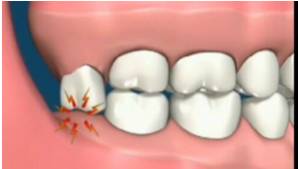

因萌出空间不足,导致智齿萌出不全而异位或阻生,牙冠部分露出牙龈,部分被牙龈覆盖。

这种智齿的牙体与牙龈之间形成一个狭窄较深的盲袋,容易嵌入并积存食物碎屑和细菌,刷牙时难以清净到这个部位,加之冠部牙龈易因咀嚼食物而损伤,形成溃疡。当全身抵抗力下降、细菌毒力增强时,就可能引起牙冠周围组织炎症,出现明显的疼痛、牙冠周围软组织发炎红肿、龈瓣边缘糜烂、张口困难等症状。